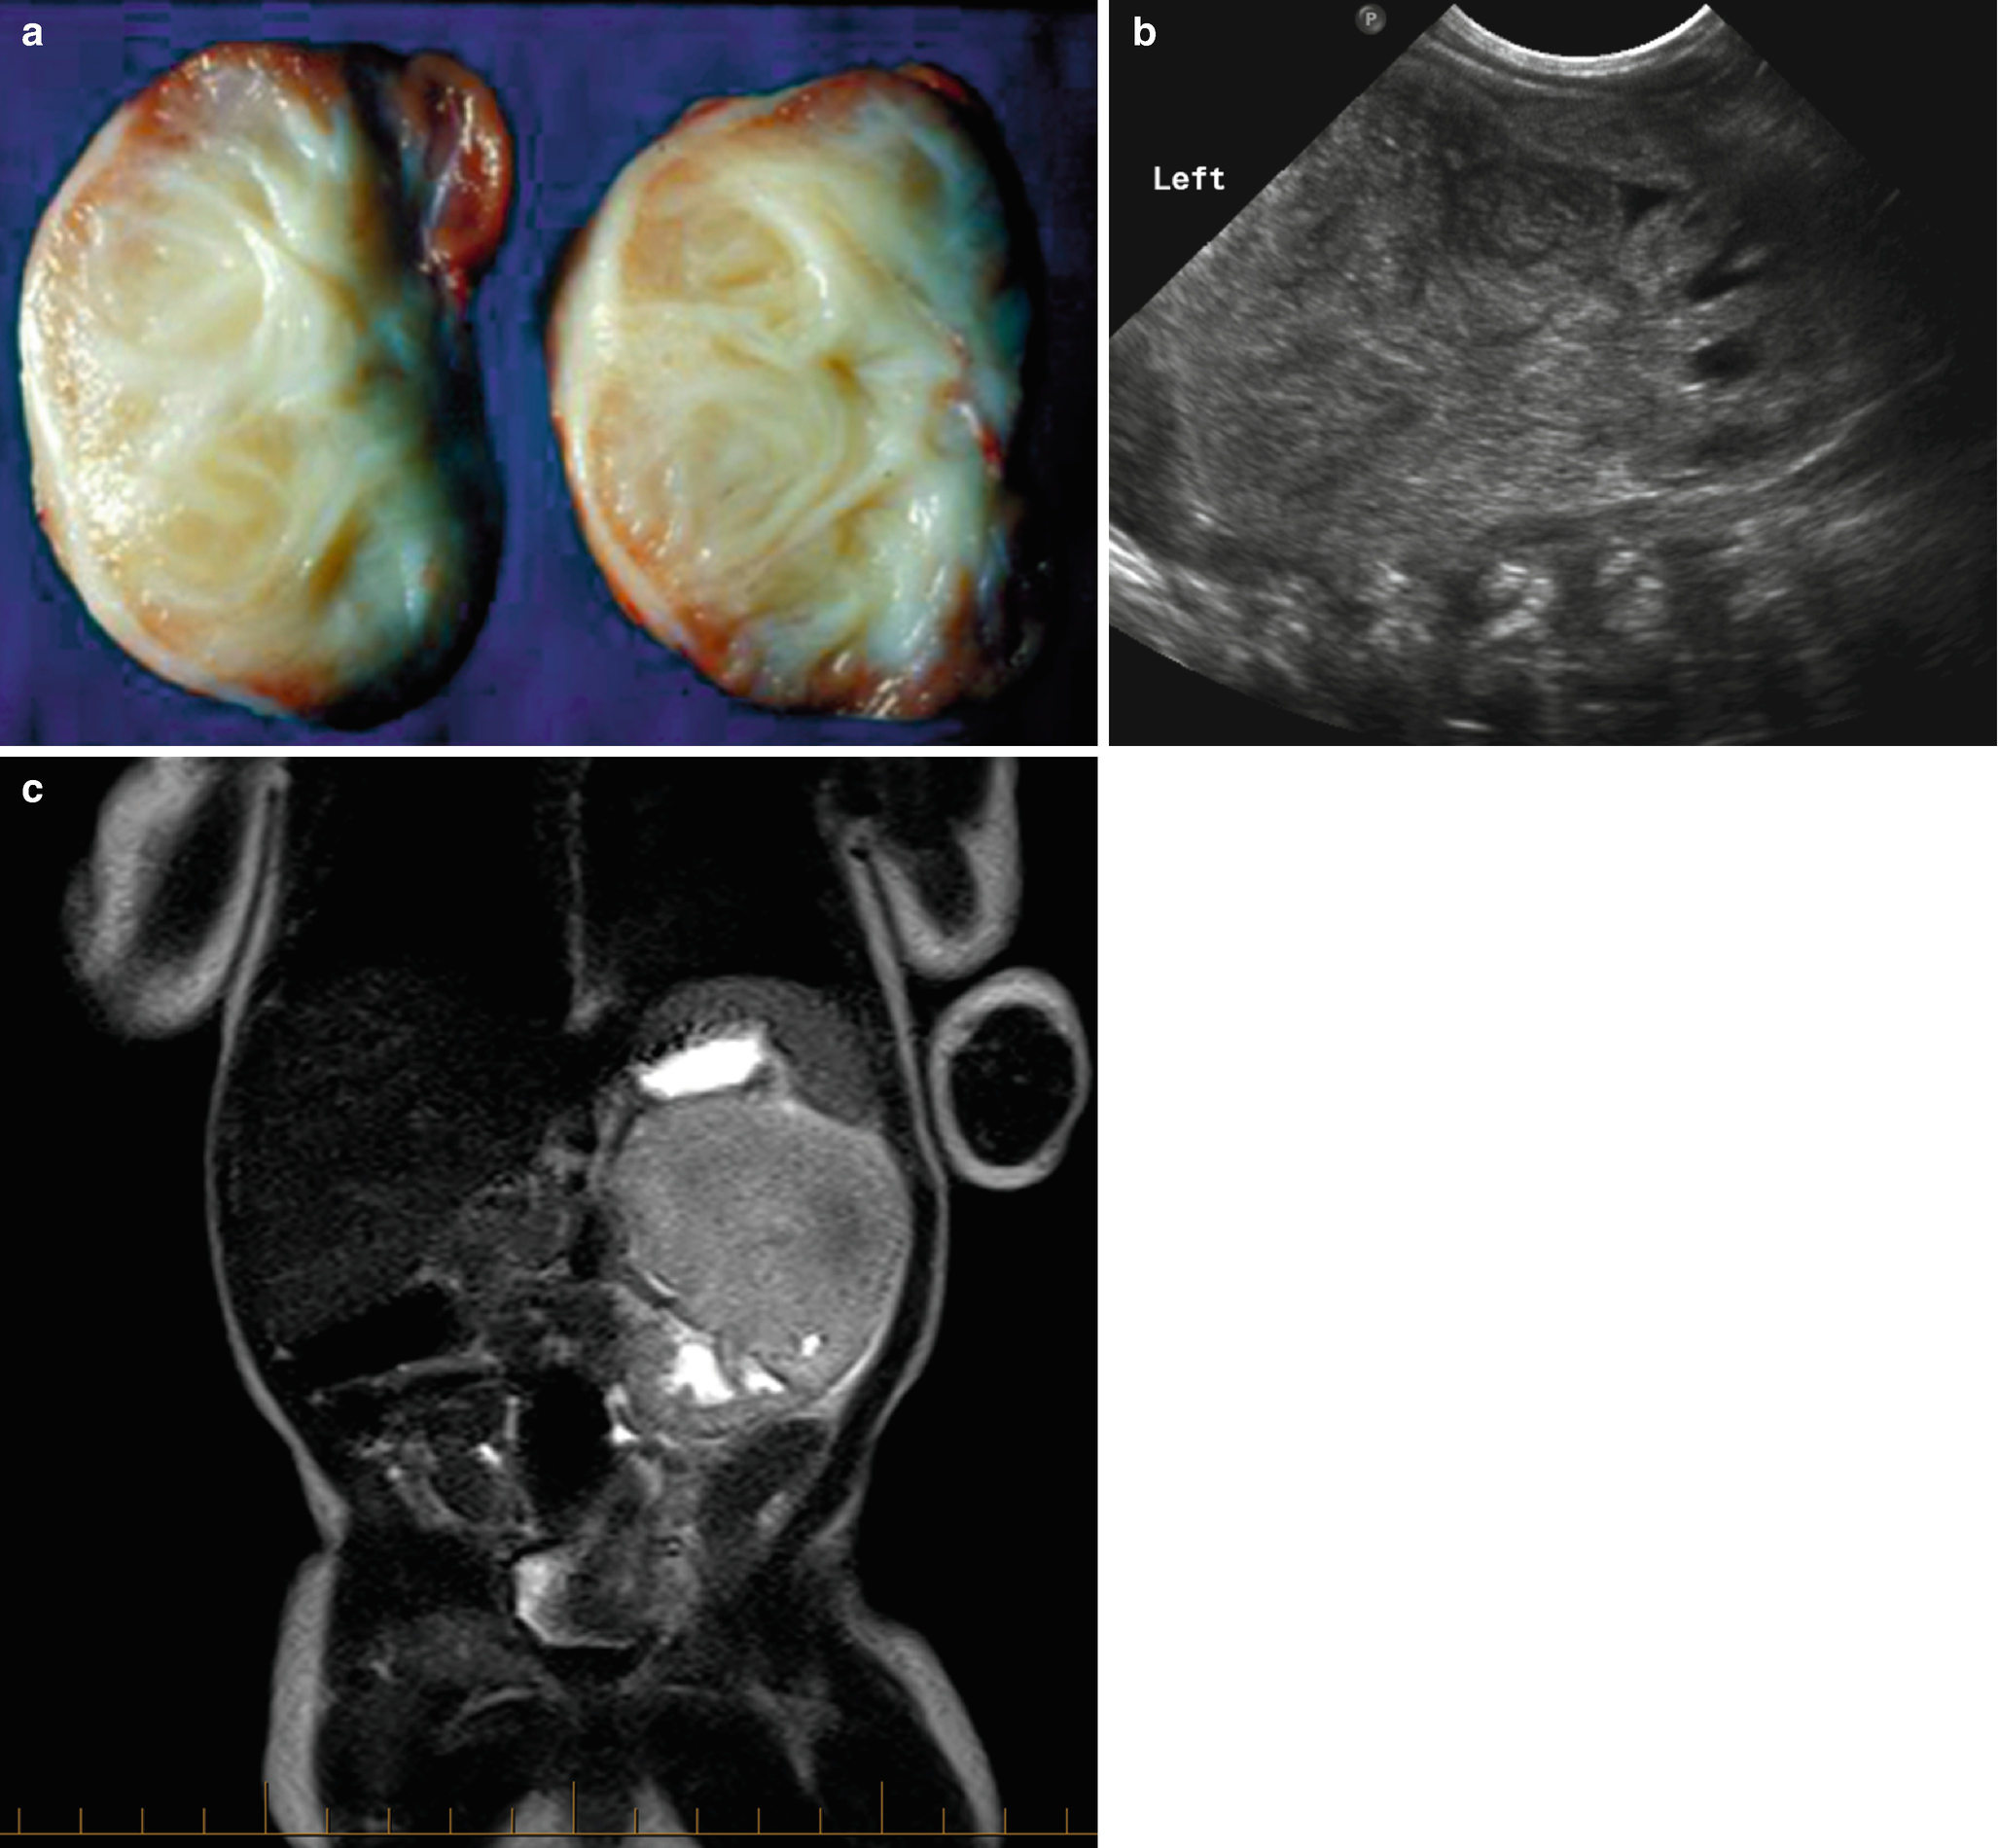

Gale Onefile Health And Medicine Document Congenital Mesoblastic Nephroma Clinical Analysis Of Eight Cases And A Review Of The Literature

Kidney Basicmedical Key

Cystic Nephroma

Etv6 Rearrangements In Patients With Infantile Fibrosarcomas And Congenital Mesoblastic Nephromas By Fluorescence In Situ Hybridization Modern Pathology